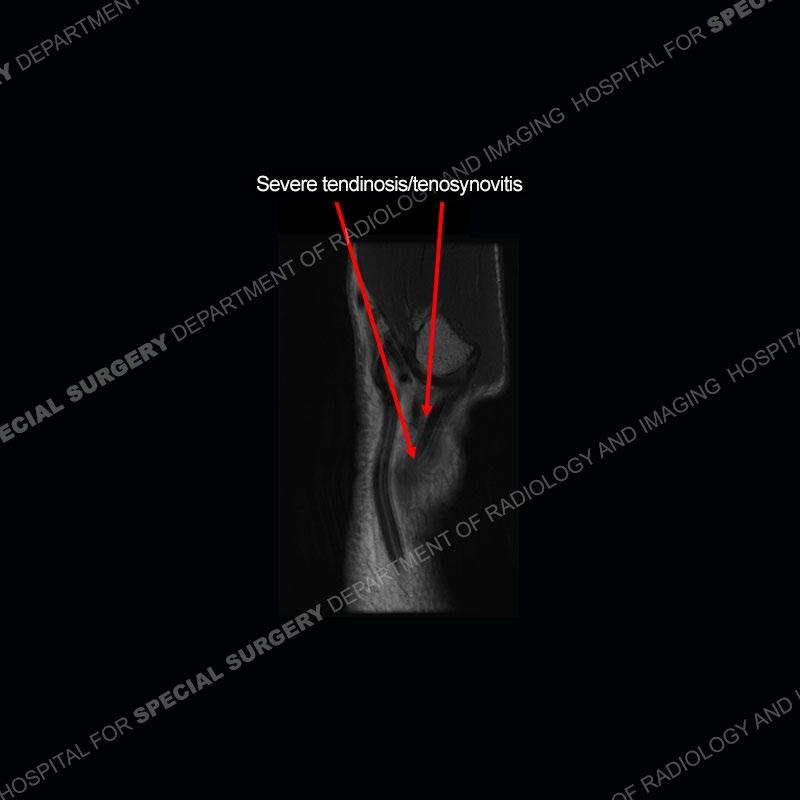

The radiographs in this case are not particularly contributory. The MRI demonstrates tenosynovitis of the first extensor compartment manifest by fluid/synovitis distention of the tendon sheaths. Multiple tendon slips are present of the abductor pollicis longus (APL) and with severe tendinosis seen of one of the tendon slips. Other areas of slightly increased signal and tendinosis are present of the components of the APL. Noted is a somewhat prominent septum separating the more dorsal extensor pollicis brevis (EPB) from the APL.

The first extensor compartment of the wrist contains the abductor pollicis longus or APL (slightly more volar) and the extensor pollicis brevis or EPB (slightly more dorsal). Tenosynovitis of this compartment is known by the eponym of DeQuervain’s tenosynovitis. In addition to tenosynovitis, tendinosis, and partial tearing can be seen. Complete disruption of the tendons is extremely uncommon. More common in women than men, this can affect almost any age patient. It is typically seen in individuals who perform repetitive gripping maneuvers or thumb overuse as can be seen in gripping a golf club or racket. The symptoms are frequently able to be managed with rest and ultrasound guided injections. Recalcitrant cases may require surgical intervention.

There can also be a partial or complete septum between the APL and EPB. This can particularly come into play with injections and positioning the needle into both sub-compartments to ensure that both tendons are bathed in the injectate.